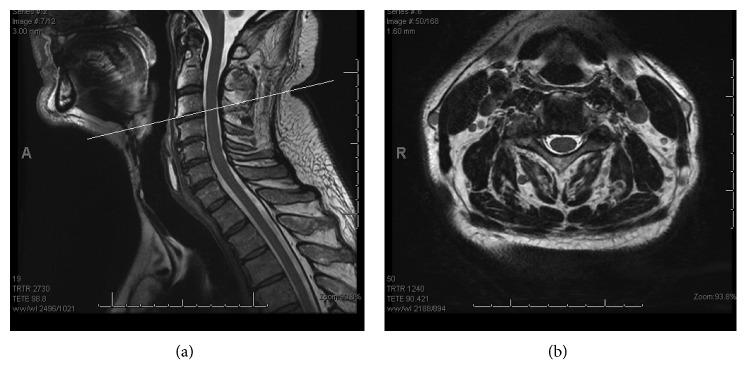

A 64-year-old man was referred to the orthopaedic service with right hemidiaphragm paralysis. He had a previous history of asbestos exposure and polio and was initially seen and investigated by the respiratory physicians. He also reported intermittent neck pain and an MRI scan showed right-sided cervical foraminal stenosis. He underwent posterior right C3/4 and C4/5 foraminotomies, and by three months postoperatively, his hemidiaphragm paralysis had resolved and his shortness of breath had also improved.

一名64岁男性因右侧半膈肌麻痹转诊至骨科。他既往有石棉接触史和小儿麻痹症病史,最初由呼吸内科医生诊治并进行检查。他还自述间歇性颈部疼痛,MRI扫描显示右侧颈椎椎间孔狭窄。他接受了右侧C3/4和C4/5后路椎间孔切开术,术后三个月,其半膈肌麻痹得到缓解,呼吸急促症状也有所改善。